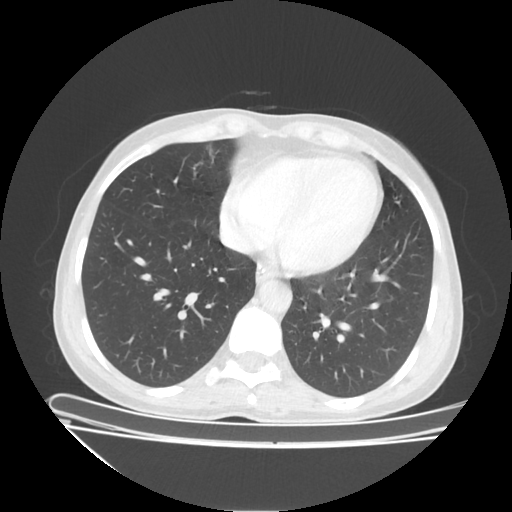

Original NATIVE CT scan (input)

Full window (WL 1023.5, WW 4095 β†’ Low βˆ’1024, High +3071)

Actual HU range: [-1024.0, 1173.0]

Lung window (WL -600, WW 1500 β†’ Low βˆ’1350, High +150)

Actual HU range: [-1350.0, 150.0]

Mediastinum window (WL 40, WW 400 β†’ Low βˆ’160, High +240)

Actual HU range: [-160.0, 240.0]